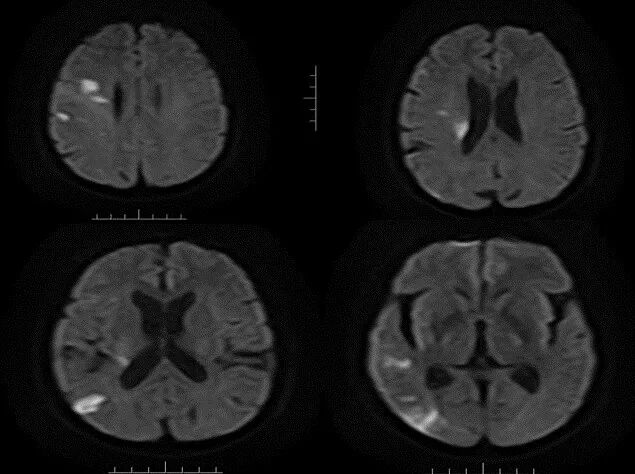

导丝怎么扩【载药时代 球扩天下】NOVA DES®颅内药物洗脱支架在大脑中动脉重度狭窄的应用二例!_https://www.jmylbn.com_新闻资讯_第22张

MRA

重要影像结论:右侧大脑中动脉M1段局限性狭窄。

DWI

重要影像结论:右侧额颞枕顶叶多发急性期脑梗死灶。